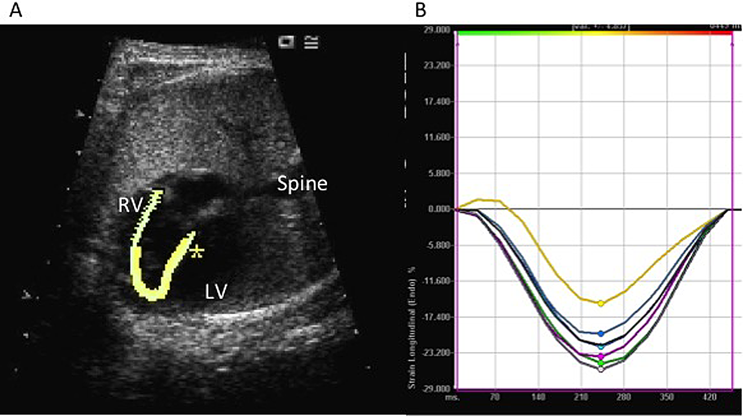

近年は3次元での解析も行われている.胎児心臓用に開発された4D超音波のspatiotemporal image correlation (STIC)法は,まず心臓全体をスキャンし画像を取り込み,心臓の周期的な変化から胎児の心拍数を検出する.読み取った心周期に合わせて3次元画像を合成し,3次元超音波画像を連続的に動かすことにより4次元超音波画像が得られる.その4次元画像を,解析ソフト(高精度体積計測機能:VOCAL)を用いて,設定した回転軸に沿って360度回転させながら,心内膜面のトレースをそれぞれの回転させた画面で行うことで,3次元での心室容積や収縮率,拍出量などの評価が可能である3)Fig. 3).

Fig. 3 Measurement of LV volume with 3D images acquired using STIC

The upper left image is a four-chamber view with easily identifiable morphological markers, and the LV surface was traced using this image. The upper right and lower left images are the orthogonal images. Therefore, the upper right image is the short-axis view of LV, and the lower right image is two the chamber view of LV. The three-dimensional models created by the Virtual Organ Computer-aided AnaLysis (VOCAL) tool after tracing LV surface images is shown at the lower left panel with its entire traced volume. (LV: left ventricle, STIC: spatiotemporal image correlation)